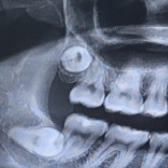

턱관절이 아프다 했고, 설문지를 작성했다. 바로 x레이를 찍었다. 사진을 다 찍고 치료실에 누워있는데 내 사진이 큼지막하게 나와 있었다. 그런데 오른쪽 턱 위아래가 좀 이상해 보였다.

인터넷이라는 광활한 파도 같은 공간에 나의 신체흔적을 남기고 싶진 않았지만 이걸로는 나를 특정짓지 못할 것 같아서.. 이정도 사진만 남겨둔다.

치아에 관해서 아무것도 모르는 나였지만 이건 딱 봐도 모양이 괴랄한 사랑니였다.

하지만 의사의 농담도 헛으로 듣다가는 큰코다칠 게 뻔하기에.. 사랑니를 뽑는다는 병원 여러 군데에 내 엑스레이 시진을 보내며 상담을 했다. 결론은 신경과 가깝다고 죄다 거절. 대학병원을 가란다. 그때서야 깨달았다. 그저 농담이 아니구나. 진짜 대학병원 각이구나..

x레이를 다시 찍었다. (경황이 있다면 이전 병원에 찍었던걸 복사해오면 좋다. 물론 너무 오래된 것 말고 사랑니가 보이는 최근 엑스레이만!) 아래쪽은 신경과 가까워 신경마비의 위험이 있고 위쪽은 상악동과 접해있어 천공 가능성이 있다고 한다.